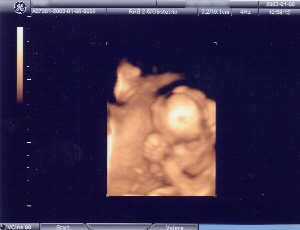

今日の胎児の写真は、いつものモノクロに加えてカラーもあります。

カラーの写真は、顔や手を握ってるところが分かります。